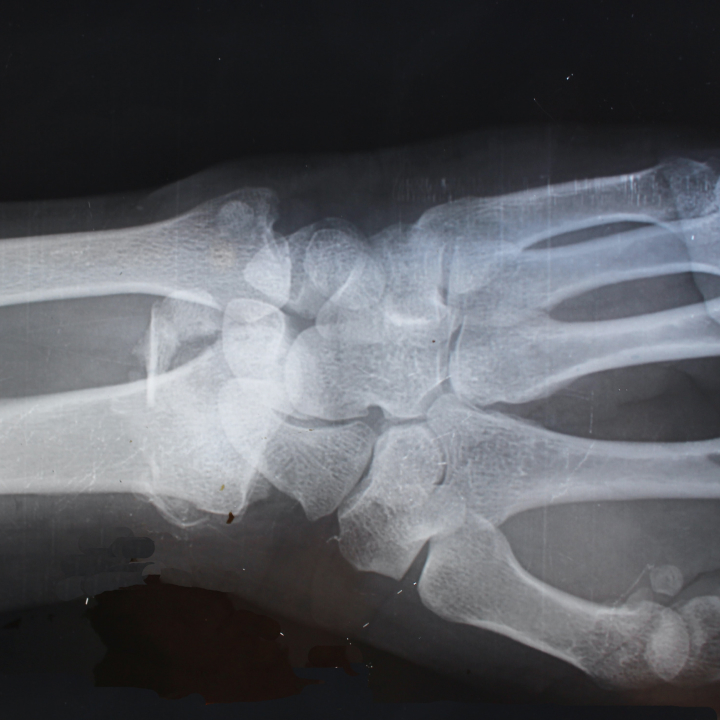

골감소증은 골밀도 감소를 유발하는 의학적 상태로, 골다공증과 골절이 발생할 위험이 있습니다. 골감소증 수치를 확인하는 가장 좋은 방법은 DEXA 스캔이라고도 하는 골밀도 검사를 받는 것입니다.

DEXA 스캔은 X-레이를 사용하여 신체의 특정 부위, 일반적으로 엉덩이와 척추의 골밀도를 측정하는 비침습적 검사입니다. 의사 사무실이나 전문 영상 센터에서 할 수 있는 빠르고 고통 없는 절차입니다.